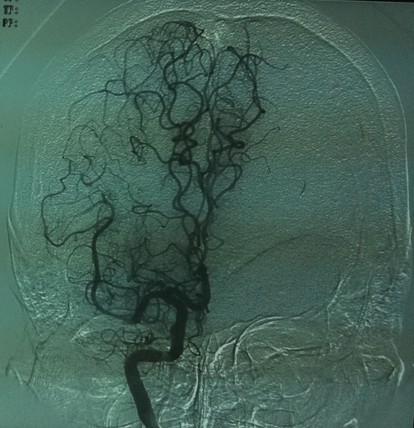

在微导丝引导下通过微导管进行接触性动脉溶栓

35mg r-tPa溶栓后见右侧颈内动脉开通,大脑前及大脑中动脉显影良好